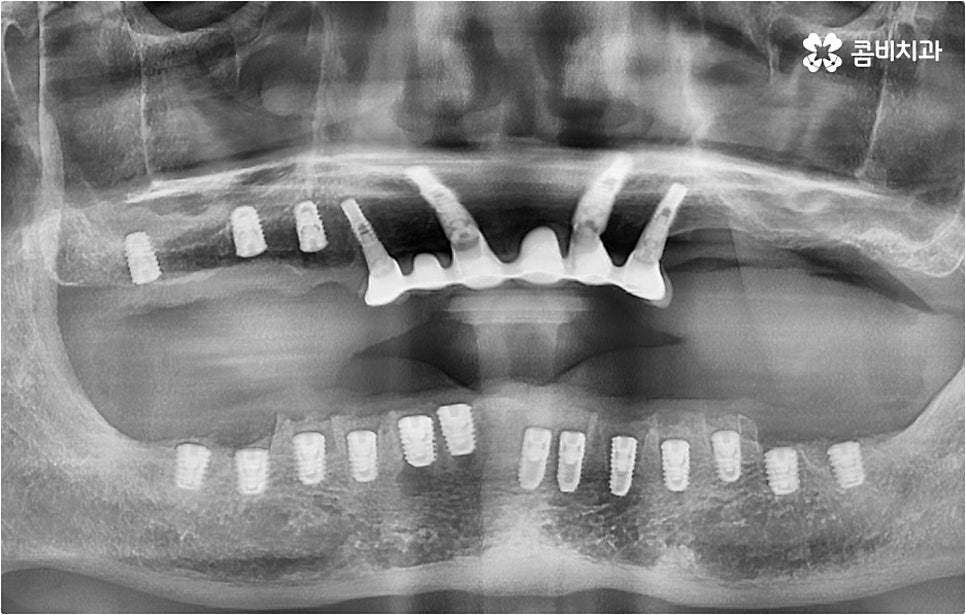

아무 것도 없는 상태에서 제대로 저작 기능을 발휘할 수 있도록 다시 구강 내부를 재현하는 전악임플란트 는 굉장히 고난도에 속하는 치료이기 때문에 충분한 임상 경험을 가지고 있는 숙련된 의료진과 함께 하실 필요가 있어요. 전악임플란트 방식이 빠진 영구치 자리마다 다 임플란트를 식립하는 것이 아니라, 상하악 각각에 8~12개 정도로 필요한 최소한의 인공 치근을 심고 그 사이 사이는 브릿지 방식으로 보철물을 연결하는 것이기 때문에 저작력을 골고루 분담하여 안정적인 지속성을 높일 수 있도록 환자 개개인의 상태에 맞게 인공 치근의 위치, 각도, 간격, 심는 깊이 등을 세밀하게 설정하여 교합을 제대로 맞출 수 있는 시술자의 뛰어난 기술력과 풍부한 노하우가 요구되는 거예요.

또한 이를 위해서 치아 주변 조직과의 거리나 잇몸뼈 높이, 밀도 등을 정확하게 파악할 수 있도록 도와주는 3D CT와 같은 정밀 진단 장비를 갖추고 환자분들의 상황에 맞는 계획을 세워 무리하지 않게 진행할 수 있는 체계적인 시스템을 운용하는 치과에서 임플란트 시술을 받으실 필요가 있어요. 만약 치과내 자체 기공소를 갖추고 있다면 보철물 제작에 대한 피드백이 보다 빠르게 전달, 반영될 수 있어 환자분들이 이용하시기에 좀 더 편안하실 거예요.

이러한 사후 관리 역시 임플란트 치아의 수명에 큰 영향을 미치는 만큼 정기 검진 및 스케일링 치료를 꾸준하게 받을 수 있도록 스케줄 관리를 철저하게 해주는 치과에서 전악임플란트 시술 받으시길 권유드리고 있습니다.